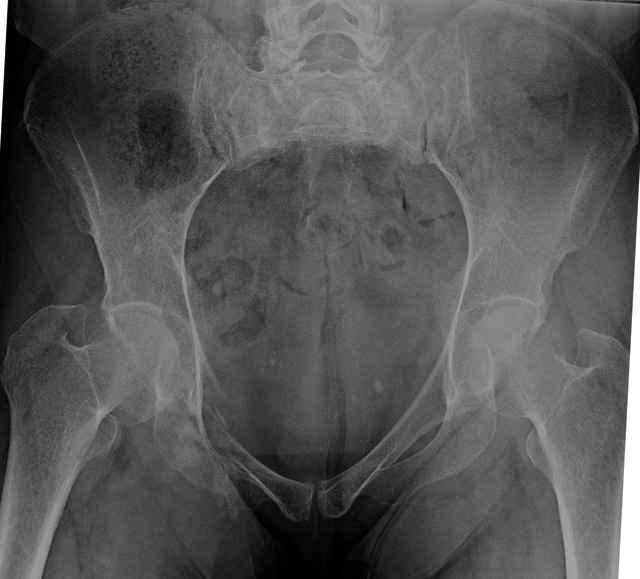

Here are a recent patient’s example slides...

54 yo Female Fell c/o Pain

Initial Films

?Instability on Exam - Limited by Pain

NonOp Initial Mgmt

3 Months After Fall

Continued Pain & Immobility

(+) Instability to Compressive Manual Exam

Pelvic CT Scan - 3 Months After Fall

Sacral Injuries

Ramus Fractures

Percutaneous Fixation

(B) Ramus-Retrograde

2 TransIliac-TransSacral

Upper Segment